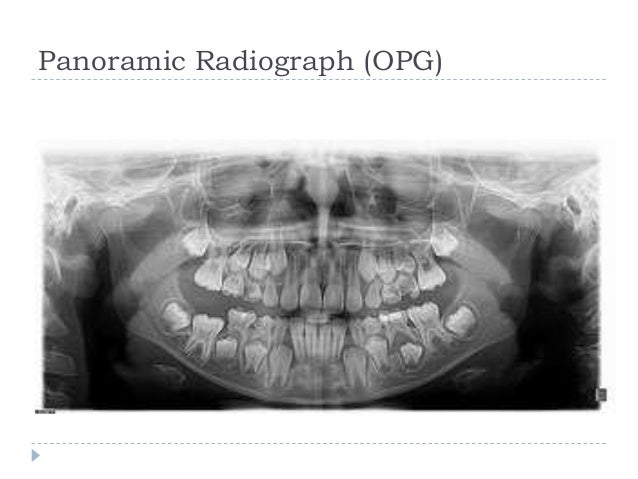

All the teeth panoramic images are not good for detecting very small cavities, but they are good at finding larger concerns like infections, impacted teeth, tumors. This method is useful in providing diagnostic information regarding identifiable landmarks, pathology, and initial. A dentist who suspects any of these. 39 companies | 109 products. Tomograms show a particular layer or slice of the. Reduced radiation exposure is one side benefit. Dental panoramic radiographs depict the full set of teeth in a single image and are used by dentists as a popular first tool for diagnosis.